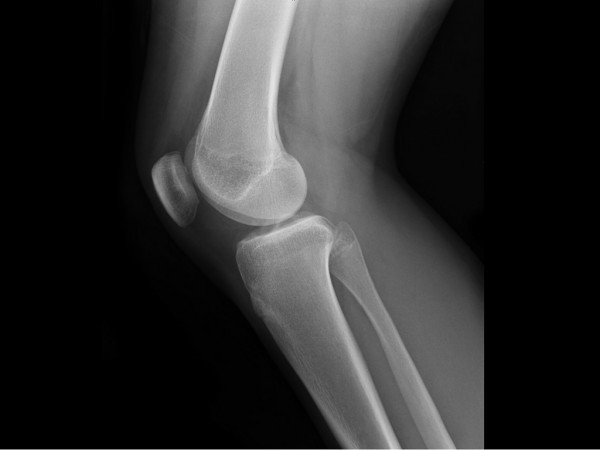

قد يكون إلتهاب الغضاريف تطور  بسبب إلتهاب المفاصل، التورم، وكذلك تصلب المفاصل ليشمل اليدين، الركبتين،  الرسغين وقد يكون هناك رؤية منخفضة بسبب إلتهاب الغضاريف . فهو من الامراض الشائعة نسبياً والتي تنطوي علي الركبتين والمفاصل والوركين والكاحلين والمرفقين جميعهم يمكن أن تتأثر .

الغضروف عبارة عن نسيج مرن موجود في جميع أنحاء الجسم ويغطي سطح المفاصل ويساعد في إمتصاص الصدمات والسماح للعظام بأن تنزلق فوق بعضها .